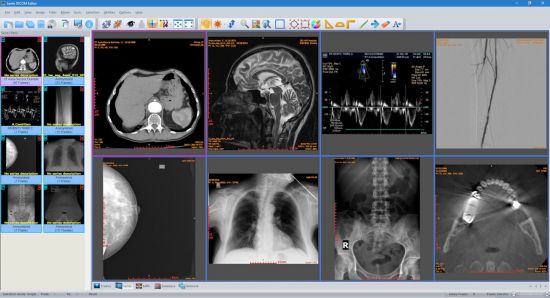

Sante DICOM Editor, para procesar, editar y generar imágenes digitales como películas, etc. tomadas en hospitales y áreas médicas

Puede realizar cualquier edición, como conversión, utilizando el software utilizado.